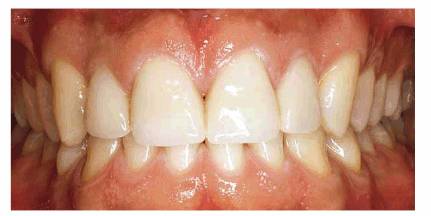

In instances where the patient has had posterior bite collapse and advanced

rehabilitation. Such a case is illustrated in Figures 23-19A, 23-19B, 23-19C, 23-19D, 23-19E, 23-19F and G, and 23-19H and I using interim bonding followed by a telescopic

fixed prosthesis.

Figure 23-19A: This 65-year-old man was embarrassed by the appearance of his front teeth.

Figure 23-19B: Using the principles previously outlined in this chapter, composite resin bonding was done to immediately improve the patient's appearance and stabilize the dentition.